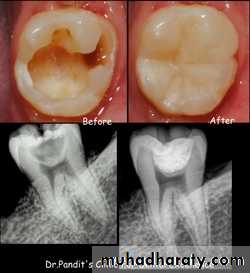

• RESULTS-BEFORE

• AND AFTER• FACTORS DETERMINING SUCCESS OF IPC.

• Remaining dentin thickness(0.5-2mm)• Choice of indirect pulp capping agent.